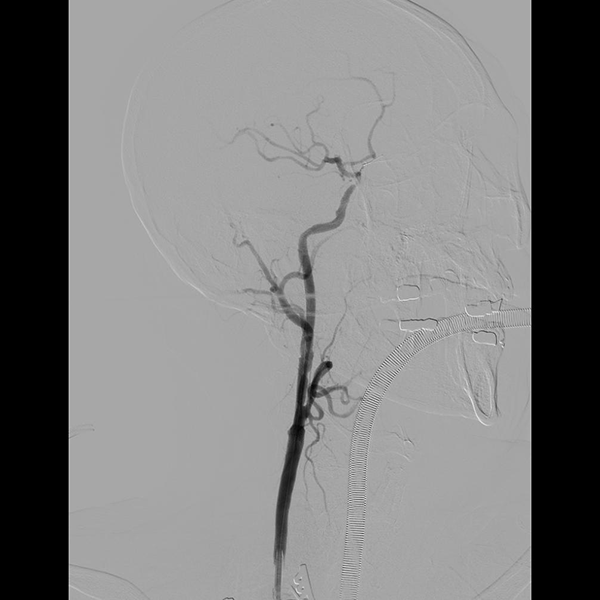

手术团队在超声引导下精准定位,通过颈部(锁骨上)3cm小切口建立操作通道及颈内动脉-股静脉转流后,成功完成右颈动脉支架植入术。整个手术过程中单侧颈总动脉阻断时间小于10分钟,术后造影显示右颈动脉通畅、支架形态良好,残余狭窄小于10%。术后患者神经系统功能完好,无并发症发生,术后第3天顺利出院。

△ 颈动脉支架置入术后影像